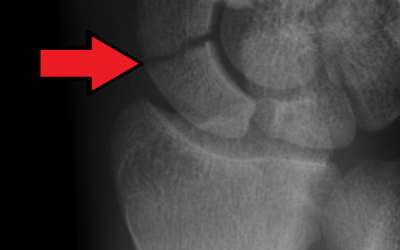

Can we avoid casting for suspected scaphoid fractures? A multicenter randomized controlled trial

Methodology: 4/5 Usefulness: 3/5 Cohen A, et al. J Orthop Traumatol. 2025 Mar 5;26(1):14. doi: 10.1186/s10195-025-00822-5. Question and Methods: Authors tested if bandaging was noninferior to casting for suspected scaphoid fractures by conducting a multicenter...